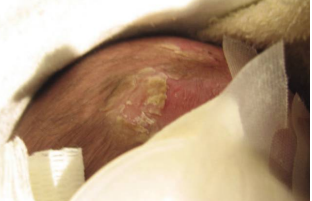

An infant with lesions on their scalp as the result of a sexually transmitted infection.

An infant with lesions on their scalp as the result of a sexually transmitted infection. Supplied/Dr., Ameeta Singh